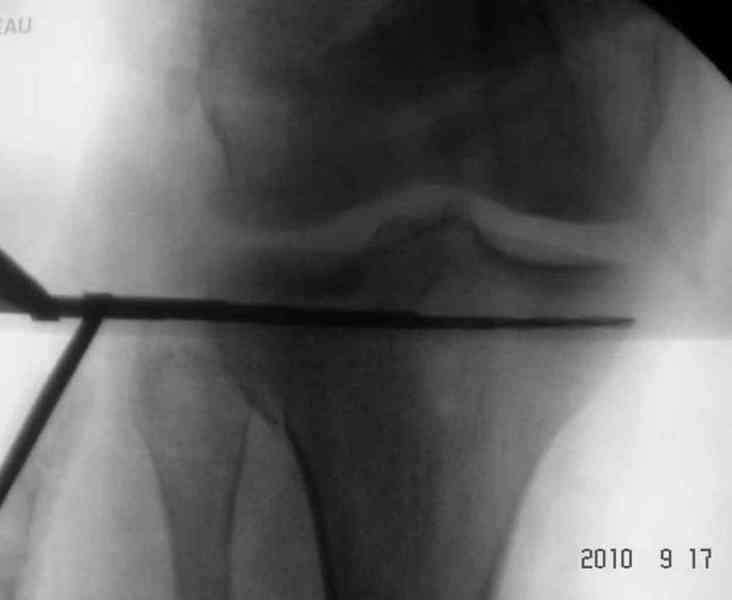

Имя     : percutaneus fixation 3.jpg

Тип     : image/jpeg

Размер  : 15581 байтов

Описание: отсутствует

Url     : http://weborto.net:8080/pipermail/ortho/attachments/20100926/dbcec959/attachment-0022.jpg

----------- УМЕДХЭБС ЮБУФШ -----------

Вложение не в текстовом формате было извлечено…

Имя     : percutaneus fixation2.jpg

Размер  : 36168 байтов

Url     : http://weborto.net:8080/pipermail/ortho/attachments/20100926/dbcec959/attachment-0023.jpg